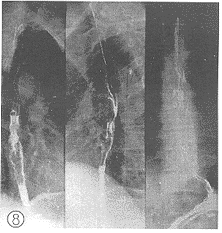

2.1 X线影像比较:每例患者在术前加速放射治疗结束后第2d及第14d分别两次摄食管钡餐造影片。由放射科、放射治疗科、胸外科3名副主任医师以上的人员读片,读片前用胶布粘住每例患者的摄片的日期,再进行“多盲法”对比观察、记录。评判标准按1981年第三届全国放射学术会议(郑州)治疗组通过的食管癌放射治疗后X线诊断标准分为4级。Ⅰ级:病变完全消失,食管壁软而光滑,蠕动及扩张良好,粘膜纹理清楚可见(图1、 2);Ⅱ级:病变基本消失,食管壁规则,钡剂能顺利通过,但管壁仍僵直或狭窄,蠕动未恢复,粘膜仍增粗(图3、 4);Ⅲ级:病变明显好转,食管病灶退缩一半以上,没有明显扭曲、成角以及突出腔外的溃疡,稠的钡剂能通过(图5、 6);Ⅳ级:病变残留或恶化,病灶消退不到一半或成角,扭曲明显或有突出腔外的溃疡,钡剂通过极差(图7、 8)。118例术前加速放射治疗后不同时间的X线影像变化结果中,从Ⅲ、Ⅳ级病例上升为Ⅱ、Ⅲ级者最多,分别达 37.8%(17/45)和43.8%(7/16);但未发现越级上升和降级病例。

图5 食管胸上段癌,食管粘膜破坏并龛影

, 百拇医药

图6 加速放射治疗第14d,商灶管壁轮廓较前规则

图7 食管中段癌髓质型

图8 放射治疗14d仍示病灶残留,病灶消退不足1/2。